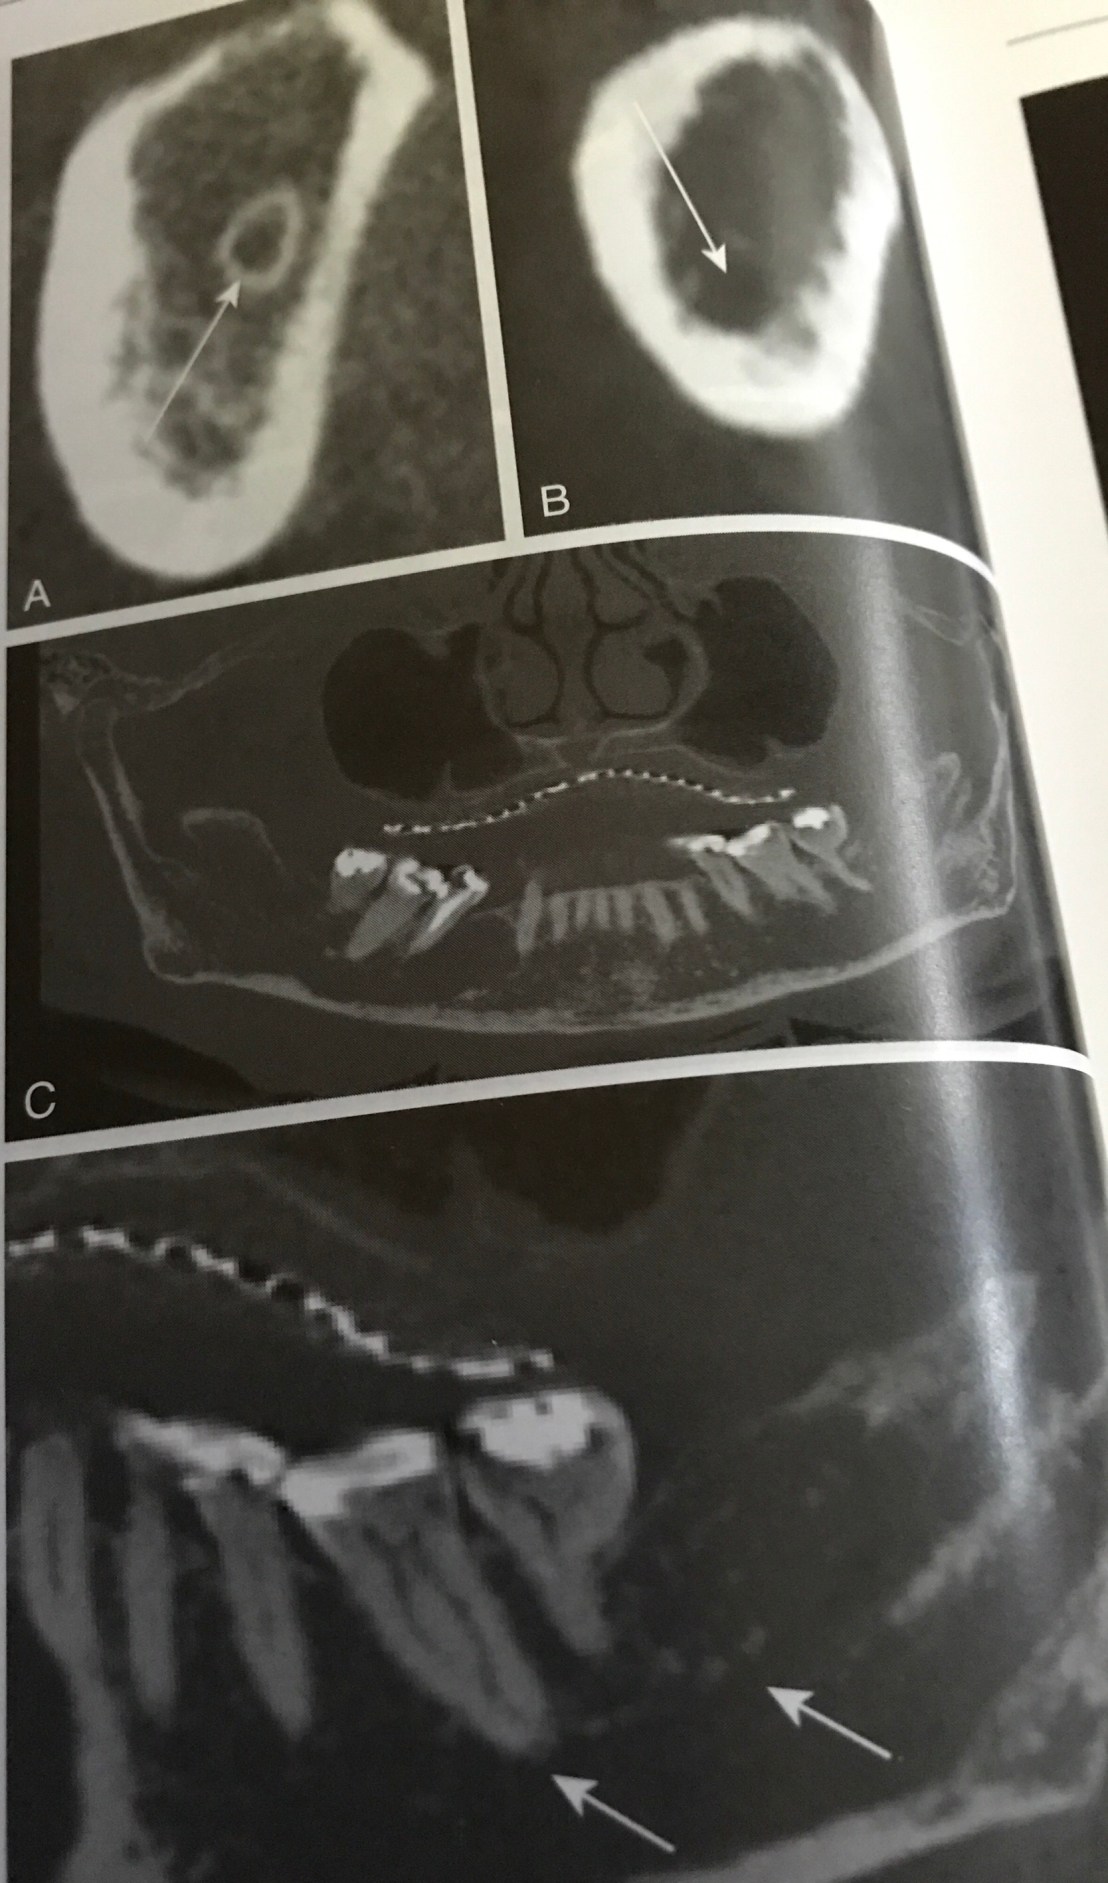

CBCT แสดงการ locate Mandibular canal

รูป A ภาคตัดขวางแสดง Mand canal มีขอบ calcify สีขาวล้อมรอบชัดเจน

รูป B ประมาณ 30% ของผู้ป่วย เราจะไม่พบ cortical bone lining รอบ canal เหมือนในรูป A ครับ

รูป C และ D คือ Panoramic view ของ CBCT